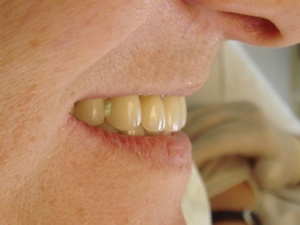

Cas terminé avec la prothèse maxillaire.

Nous avons pu réaliser une prothèse mandibulaire fixe sur une patiente présentant une atrophie osseuse mandibulaire postérieure e restaurer les dents jusqu'à la première prémolaire.

Après quelques mois d'adaptation, une prothèse similaire a été réalisée au maxillaire.